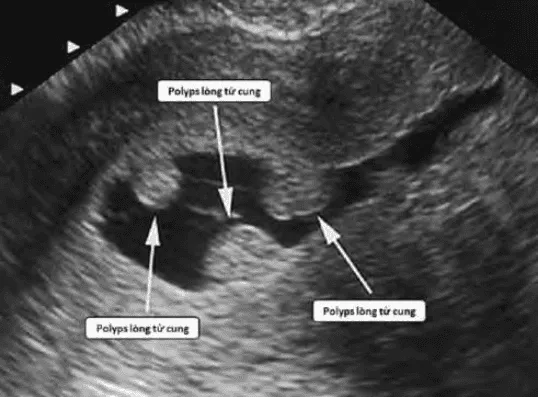

Hình ảnh “Siêu âm bơm nước của polyps buồng tử cung (SIS)”.

- Siêu âm bơm nước buồng tử cung (SIS) được chỉ định khi nghi ngờ có tổn thương nội mạc tử cung (polyp, dính buồng tử cung…).